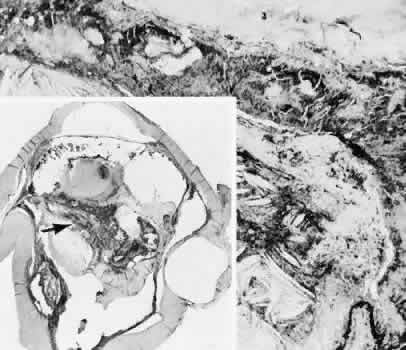

Cyclocryotherapy, cyclodiathermy (Fig. 20), and therapeutic ultrasonography apply energy directly to the pars plicata and cause lysis of the ciliary muscle and occlusion of the vascular supply, leading to extensive necrosis and scarring. Pressure lowering is accomplished by a reduction of aqueous production. Heat applied to the sclera may cause necrosis and localized scleral thinning. Cold applied to the sclera, unless extreme, does not cause any clinical or histologic changes.

Fig. 20. Cyclodiathermy treatment of the ciliary body to control glaucoma. A. Gross photograph illustrates extensive areas of depigmentation mainly in the region of the pars plana (arrows) rather than the pars plicata. B. Light micrograph of the region of the pars plana illustrates an extensive area of tissue degeneration of the pars plana (between arrows) in the late postoperative course. C. Light micrograph of the destructive effects of cyclocryotherapy also in the region of the pars plana and pars plicata. The ciliary epithelium in the early postoperative period is necrotic and cystic. (Hematoxin-eosin stain; A, × 8; B, × 16.)

Cyclodialysis (Fig. 21) creates a cleft between the sclera and the longitudinal muscle of the ciliary body. Aqueous passes directly from the anterior chamber into the suprachoroidal space. Histologically, the longitudinal muscle of the ciliary body is disinserted from the scleral spur. Diaphanous tissue often is present in the suprachoroidal space along the route of filtration. The presence of this tissue differentiates the surgical site from artifactual disinsertion of the ciliary body, which is a common artifact of ocular tissue preparation.

Fig. 21. Light micrograph of cyclodialysis. The region of the surgical cleft between the longitudinal muscle of the ciliary body and the sclera (arrow) is filled with delicate fibrous tissue. Note the posterior location of the anterior face of the ciliary body and the angle recesses in relationship to the scleral spur (S).